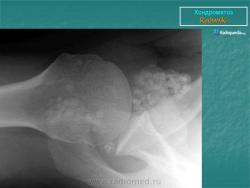

Хондроматоз внутрисуставной (синовиальный)

Приложения:

1.ho_.slayd279.jpg2.ho_.slayd280.jpg3.ho_.slayd281.jpg